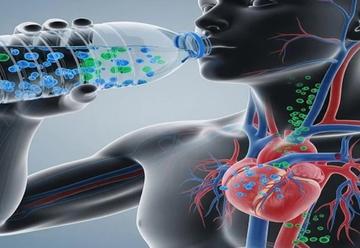

Kalbinizde plastik olabilir mi? Uzmanından kritik açıklama

Kardiyoloji Uzmanı Prof. Dr. Bülent Demir, mikroplastiklerin yalnızca sindirim sistemini değil; kalp, beyin ve böbrekleri de tehdit ettiğini belirtti. Mikroplastiklerin vücutta iltihap ol...